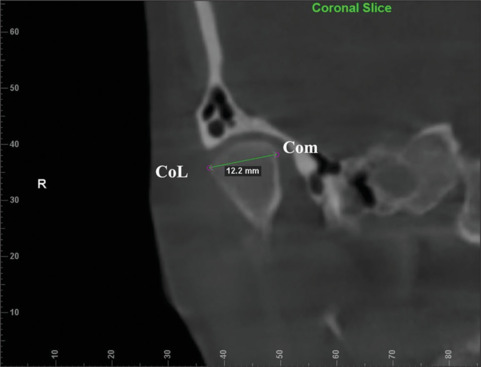

Materials and methods: CBCT images of 84 patients were collected for the study. FACAD (ILEXIS AB, Linköping, Sweden) software was used to divide the patients into Class I, II, and III skeletal malocclusions. Dolphin software was used to measure the width, length, and height of condyles and glenoid fossa of the patients from the CBCT images. The Shapiro-Wilk test was used to check normality. ANOVA test was performed to assess the statistical significance of the results between the 3 groups.

Results: The sample consisted of 30 patients with class I skeletal relation, 34 patients with class II relation, and 20 patients with class III relation. In class I relation, the average condylar height is found to be 16.32 mm ± 2.16 mm, width is 16.47 mm ± 2.61 mm, and length 7.65 mm ± 1.5 mm. The average dimensions of the glenoid fossa in class I skeletal relation were measured to be 19.93 mm ± 2.64 mm in width, 13.93 mm ± 1.45 mm in length, and 6.4 mm ± 1.49 mm in height.